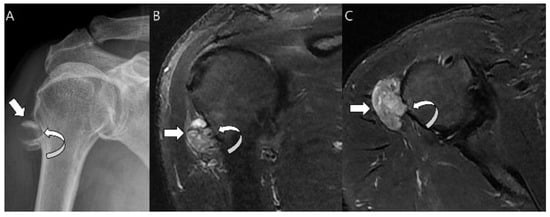

3.1. Distinction between Enchondroma and ACT

3.3. Distinction between ACT/CS1 and High-Grade Chondrosarcoma